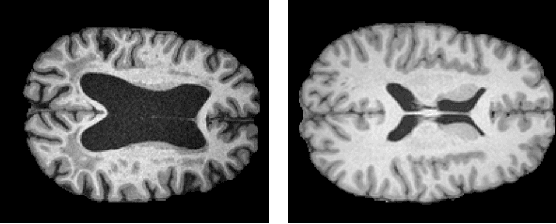

Abstract:Unsupervised anomaly detection in Brain MRIs aims to identify abnormalities as outliers from a healthy training distribution. Reconstruction-based approaches that use generative models to learn to reconstruct healthy brain anatomy are commonly used for this task. Diffusion models are an emerging class of deep generative models that show great potential regarding reconstruction fidelity. However, they face challenges in preserving intensity characteristics in the reconstructed images, limiting their performance in anomaly detection. To address this challenge, we propose to condition the denoising mechanism of diffusion models with additional information about the image to reconstruct coming from a latent representation of the noise-free input image. This conditioning enables high-fidelity reconstruction of healthy brain structures while aligning local intensity characteristics of input-reconstruction pairs. We evaluate our method's reconstruction quality, domain adaptation features and finally segmentation performance on publicly available data sets with various pathologies. Using our proposed conditioning mechanism we can reduce the false-positive predictions and enable a more precise delineation of anomalies which significantly enhances the anomaly detection performance compared to established state-of-the-art approaches to unsupervised anomaly detection in brain MRI. Furthermore, our approach shows promise in domain adaptation across different MRI acquisitions and simulated contrasts, a crucial property of general anomaly detection methods.

Abstract:The use of supervised deep learning techniques to detect pathologies in brain MRI scans can be challenging due to the diversity of brain anatomy and the need for annotated data sets. An alternative approach is to use unsupervised anomaly detection, which only requires sample-level labels of healthy brains to create a reference representation. This reference representation can then be compared to unhealthy brain anatomy in a pixel-wise manner to identify abnormalities. To accomplish this, generative models are needed to create anatomically consistent MRI scans of healthy brains. While recent diffusion models have shown promise in this task, accurately generating the complex structure of the human brain remains a challenge. In this paper, we propose a method that reformulates the generation task of diffusion models as a patch-based estimation of healthy brain anatomy, using spatial context to guide and improve reconstruction. We evaluate our approach on data of tumors and multiple sclerosis lesions and demonstrate a relative improvement of 25.1% compared to existing baselines.

Abstract:The detection of lesions in magnetic resonance imaging (MRI)-scans of human brains remains challenging, time-consuming and error-prone. Recently, unsupervised anomaly detection (UAD) methods have shown promising results for this task. These methods rely on training data sets that solely contain healthy samples. Compared to supervised approaches, this significantly reduces the need for an extensive amount of labeled training data. However, data labelling remains error-prone. We study how unhealthy samples within the training data affect anomaly detection performance for brain MRI-scans. For our evaluations, we consider three publicly available data sets and use autoencoders (AE) as a well-established baseline method for UAD. We systematically evaluate the effect of impured training data by injecting different quantities of unhealthy samples to our training set of healthy samples from T1-weighted MRI-scans. We evaluate a method to identify falsely labeled samples directly during training based on the reconstruction error of the AE. Our results show that training with impured data decreases the UAD performance notably even with few falsely labeled samples. By performing outlier removal directly during training based on the reconstruction-loss, we demonstrate that falsely labeled data can be detected and removed to mitigate the effect of falsely labeled data. Overall, we highlight the importance of clean data sets for UAD in brain MRI and demonstrate an approach for detecting falsely labeled data directly during training.

Abstract:Lesion detection in brain Magnetic Resonance Images (MRIs) remains a challenging task. MRIs are typically read and interpreted by domain experts, which is a tedious and time-consuming process. Recently, unsupervised anomaly detection (UAD) in brain MRI with deep learning has shown promising results to provide a quick, initial assessment. So far, these methods only rely on the visual appearance of healthy brain anatomy for anomaly detection. Another biomarker for abnormal brain development is the deviation between the brain age and the chronological age, which is unexplored in combination with UAD. We propose deep learning for UAD in 3D brain MRI considering additional age information. We analyze the value of age information during training, as an additional anomaly score, and systematically study several architecture concepts. Based on our analysis, we propose a novel deep learning approach for UAD with multi-task age prediction. We use clinical T1-weighted MRIs of 1735 healthy subjects and the publicly available BraTs 2019 data set for our study. Our novel approach significantly improves UAD performance with an AUC of 92.60% compared to an AUC-score of 84.37% using previous approaches without age information.

Abstract:Purpose. Brain Magnetic Resonance Images (MRIs) are essential for the diagnosis of neurological diseases. Recently, deep learning methods for unsupervised anomaly detection (UAD) have been proposed for the analysis of brain MRI. These methods rely on healthy brain MRIs and eliminate the requirement of pixel-wise annotated data compared to supervised deep learning. While a wide range of methods for UAD have been proposed, these methods are mostly 2D and only learn from MRI slices, disregarding that brain lesions are inherently 3D and the spatial context of MRI volumes remains unexploited. Methods. We investigate whether using increased spatial context by using MRI volumes combined with spatial erasing leads to improved unsupervised anomaly segmentation performance compared to learning from slices. We evaluate and compare 2D variational autoencoder (VAE) to their 3D counterpart, propose 3D input erasing, and systemically study the impact of the data set size on the performance. Results. Using two publicly available segmentation data sets for evaluation, 3D VAE outperform their 2D counterpart, highlighting the advantage of volumetric context. Also, our 3D erasing methods allow for further performance improvements. Our best performing 3D VAE with input erasing leads to an average DICE score of 31.40% compared to 25.76% for the 2D VAE. Conclusions. We propose 3D deep learning methods for UAD in brain MRI combined with 3D erasing and demonstrate that 3D methods clearly outperform their 2D counterpart for anomaly segmentation. Also, our spatial erasing method allows for further performance improvements and reduces the requirement for large data sets.